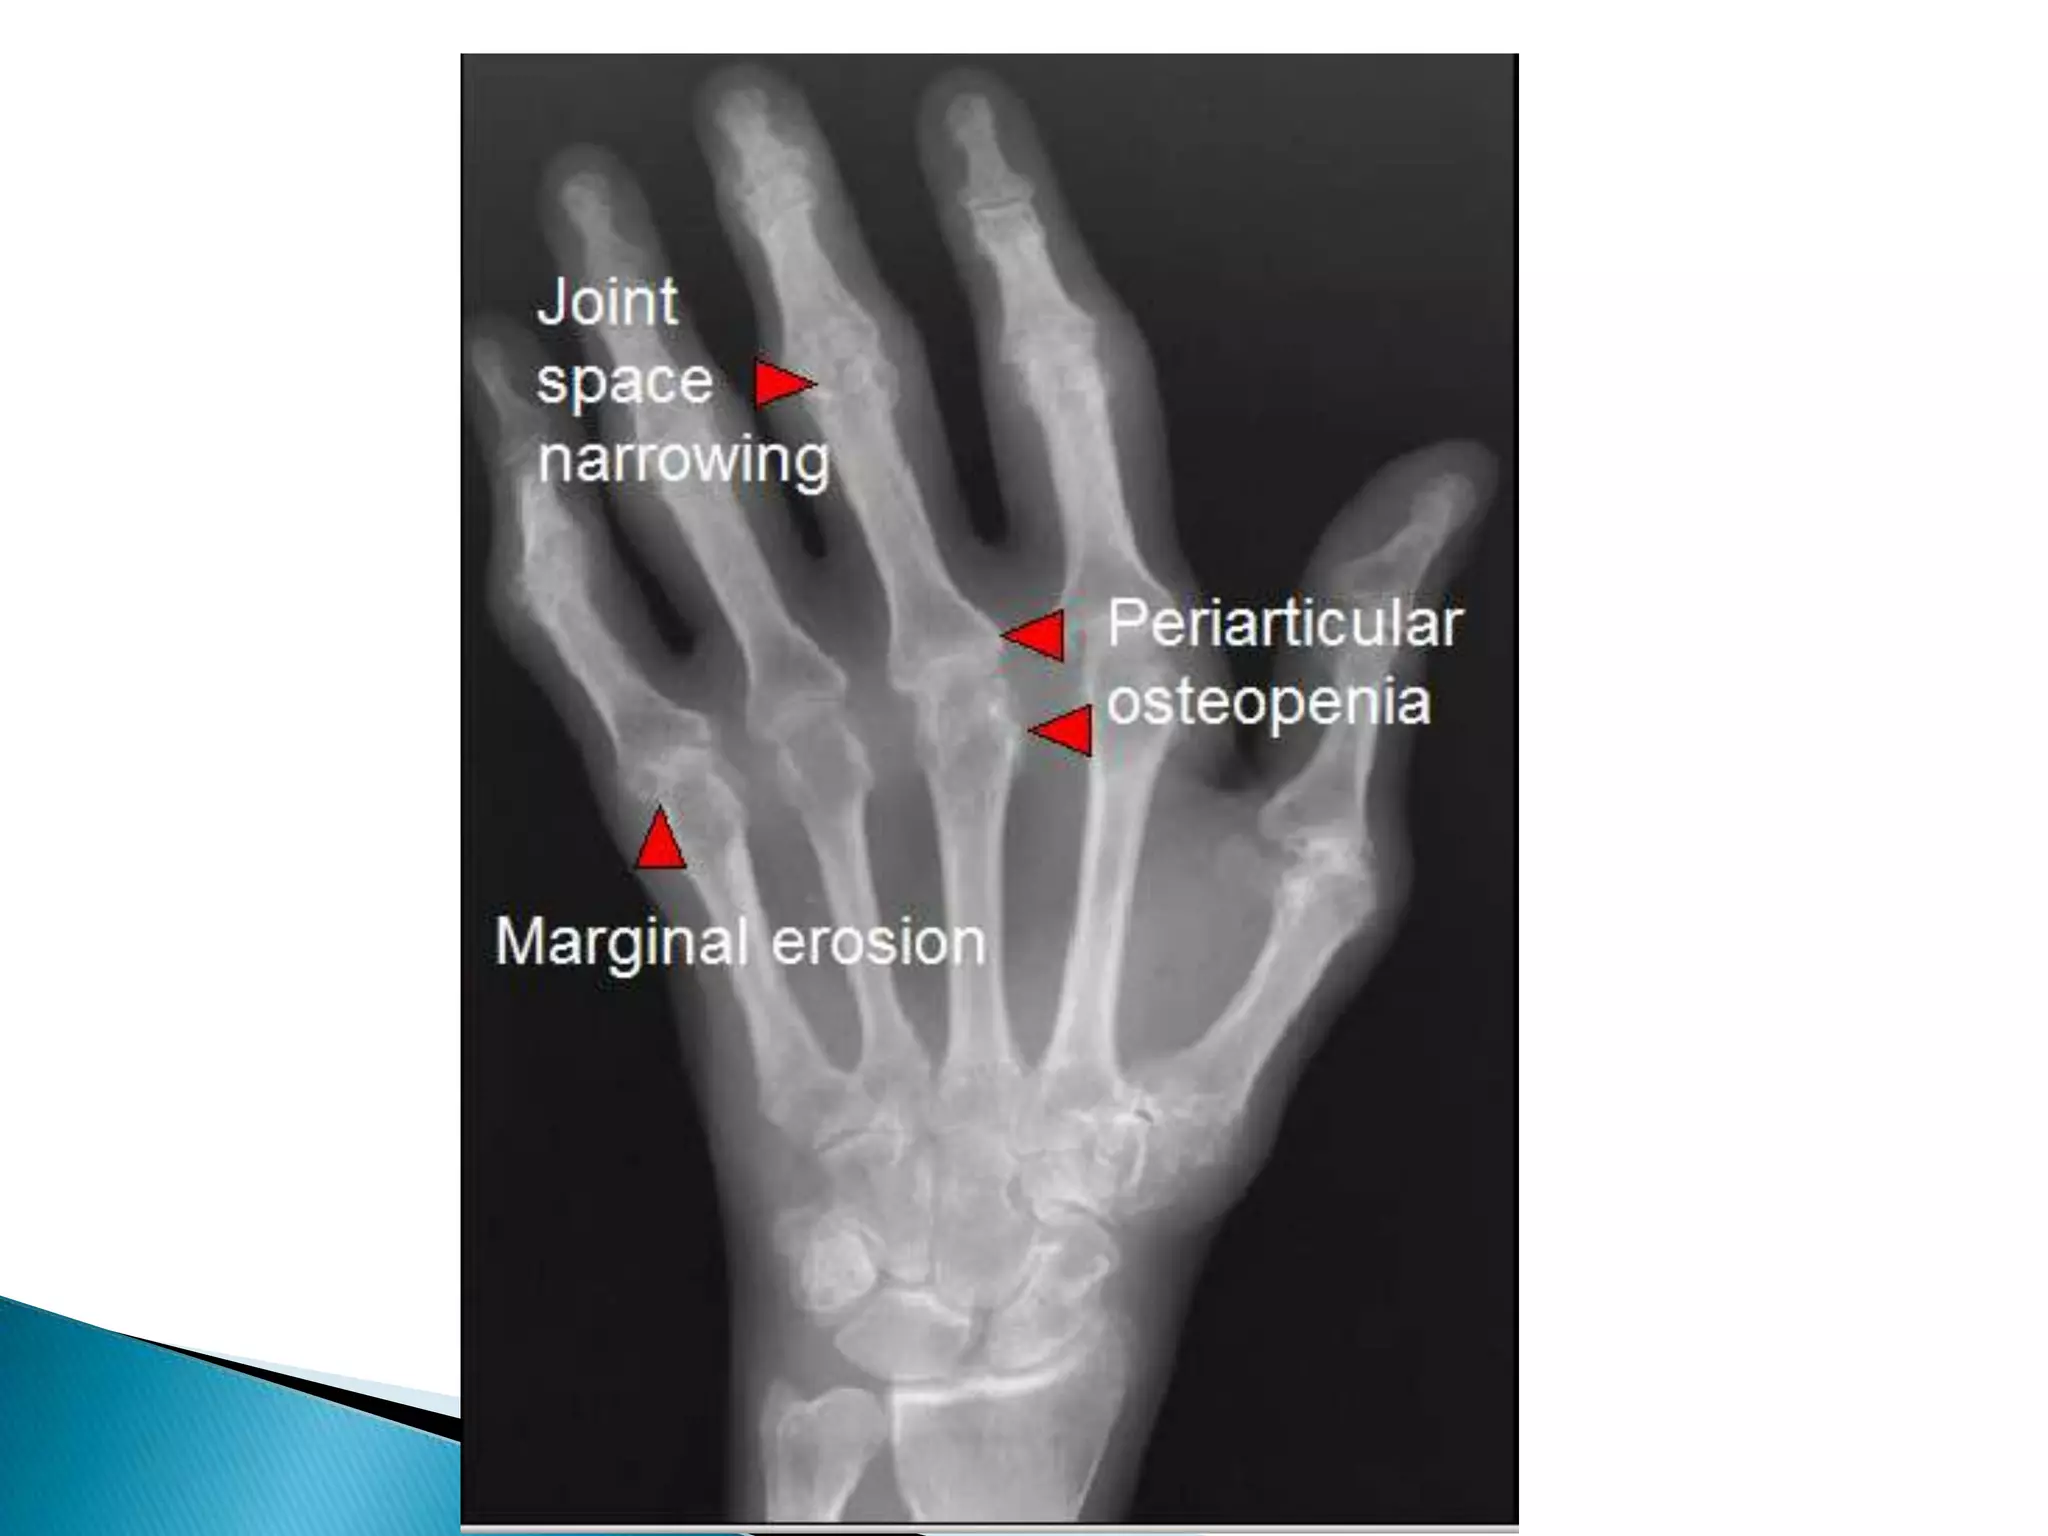

1-Joint space narrowing; It occur in all forms of joint diseases except avascular necrosis.

2-Soft tissue swelling;Periarticular soft tissue swelling is  a feature of inflammatory  & infective arthritis.Discrete asymmetrical periarticular soft tissue swelling can be seen in gout due to gouty tophi

Radiological features of RA

1-Joint space narrowing;It occur in all forms of joint diseases except avascular necrosis.

2-Soft tissue swelling;Periarticularsoft tissue swelling is a feature of inflammatory & infective arthritis.Discrete asymmetrical periarticular soft tissue swelling can be seen in gout due to gouty tophi